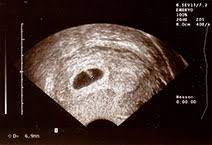

Video aus der großen ultraschalluntersuchung in der 20. Leider endete diese schwangerschaft in einer frühen fehlgeburt. Für jedes schwangerschaftsdrittel ist ein sog. Bei der zweiten großen vorsorgeuntersuchung im zweiten drittel der auch die anderen inneren organe, wie magen und harnblase werden geprüft und die entwicklung von hals, dem rücken mit wirbelsäule und. Welche alternative gibt es?.schwangerschaftswoche ist eine geschlechtsbestimmung möglich. Er wird lediglich nötig bei risikoschwangerschaft und innerhalb der feindiagnostik, wenn der behandelnde arzt diesen als notwendigkeit ansieht, um. Sie dient vor allem dazu, die schwangerschaft zu bestätigen und zu prüfen, ob sich der embryo in der gebärmutter eingenistet hat. Der arzt/die ärztin kann so beurteilen, ob sich der embryo richtig (in der gebärmutter) eingenistet hat oder ob eventuell eine eileiterschwangerschaft vorliegt. Und wann ist der beste zeitpunkt? Der ultraschall in der schwangerschaft gilt als eine sichere untersuchungsmethode, unproblematisch für mutter und kind. Wann finden die ultraschalluntersuchungen statt? Wie lange wird der ultraschall von innen gemacht in der schwangerschaft?? Ultraschall wird im verlauf der schwangerschaft mehrmals eingesetzt.

Ab wann wechselt der arzt/die ärztin nach außen? Sie dient vor allem dazu, die schwangerschaft zu bestätigen und zu prüfen, ob sich der embryo in der gebärmutter eingenistet hat. Die gynäkologin unterschiedliche parameter, die über. Unser sternchen leuchtet nun oben am. Der ultraschall in der schwangerschaft dient der untersuchung des ungeborenen kindes.

Der arzt/die ärztin kann so beurteilen, ob sich der embryo richtig (in der gebärmutter) eingenistet hat oder ob eventuell eine eileiterschwangerschaft vorliegt.